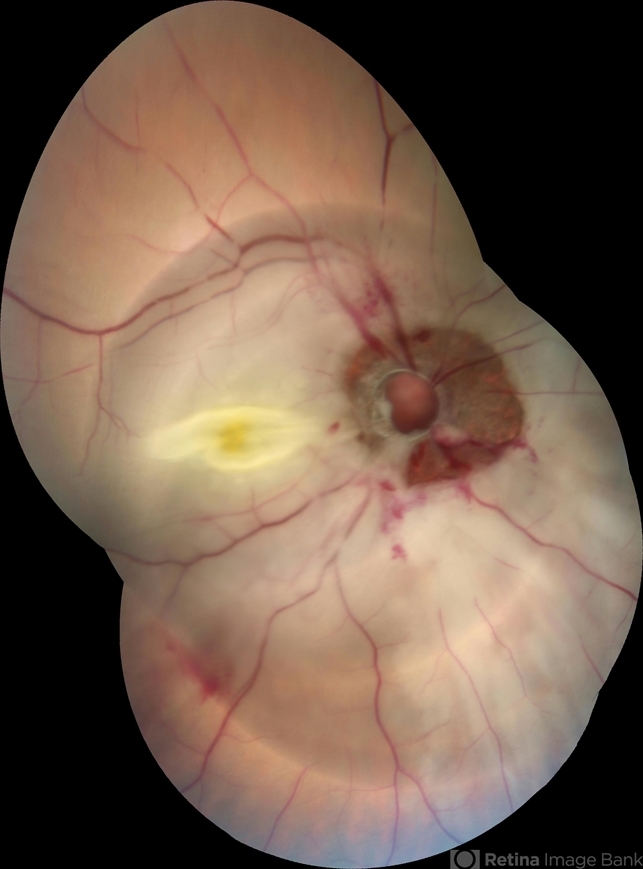

- avulsion, central retinal artery occlusion (CRAO)

- Right eye fundus picture of a 24-year-old male patient who suffered blunt trauma 7 days back with a wooden stick . He presented with NLP vision with a non reacting dilated pupil. Fundus montage picture shows ONH avulsion,CRAO,peripapillary resolving hemorrhages and cicatricial tissue at the edge.